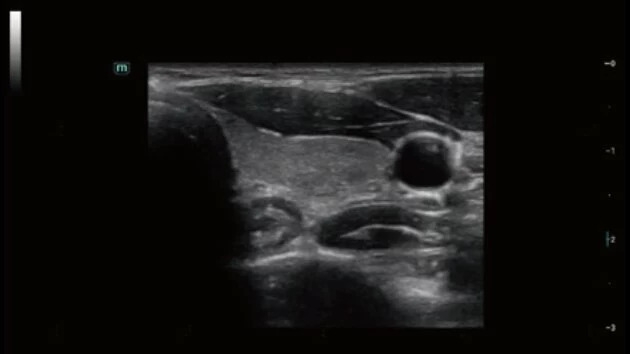

- Широкий спектр клинических исследований

- Расширенные возможности визуализации различных органов и тканей